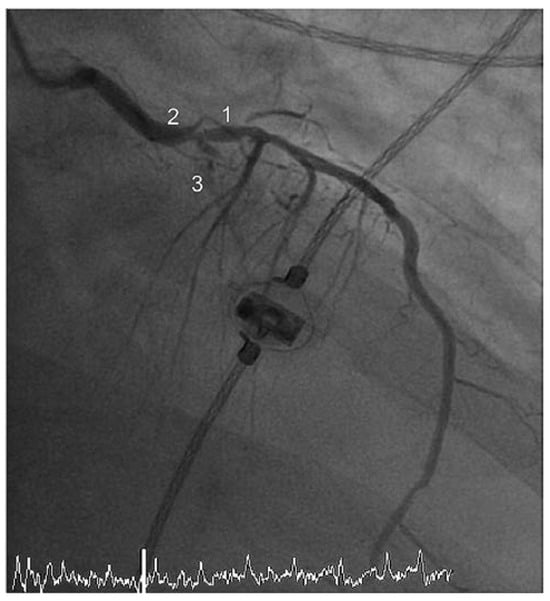

Case report A 22-year-old male experienced a presyncopal spell while studying for a university examination [...]